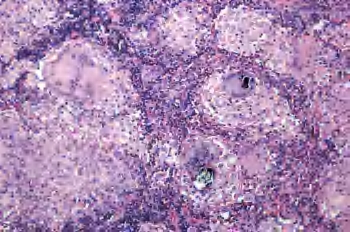

Schaumann小体最大径20~50μm,存在于巨细胞内或组织间隙,嗜苏木素着色,组织化学显示其中含铁或钙;星状体大小5~35μm,为蜘蛛状放射形结构,中央为2~4μm的核心,从此核心针状刺向周围放射。此两种小体是非诊断特异性的(图3-15至图3-17)。

图3-17 结节病中心是Schaumann小体